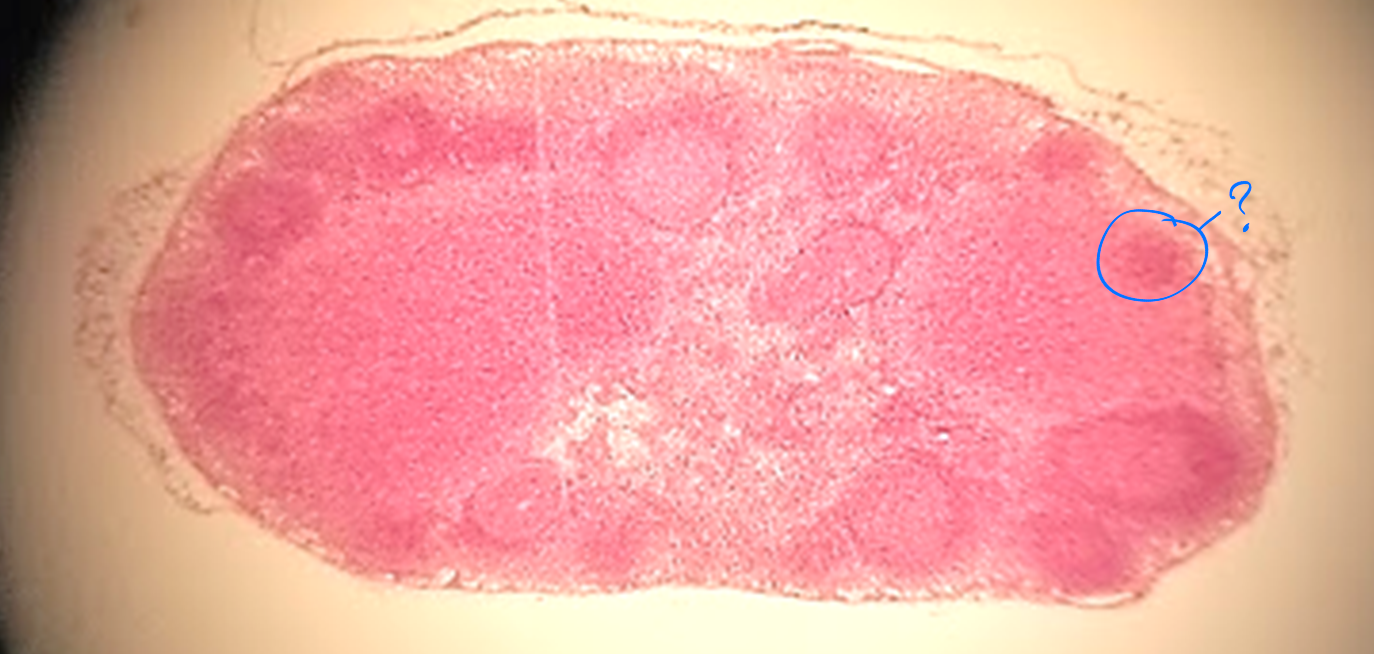

red pulp of spleen

what is outlined?

white pulp of spleen